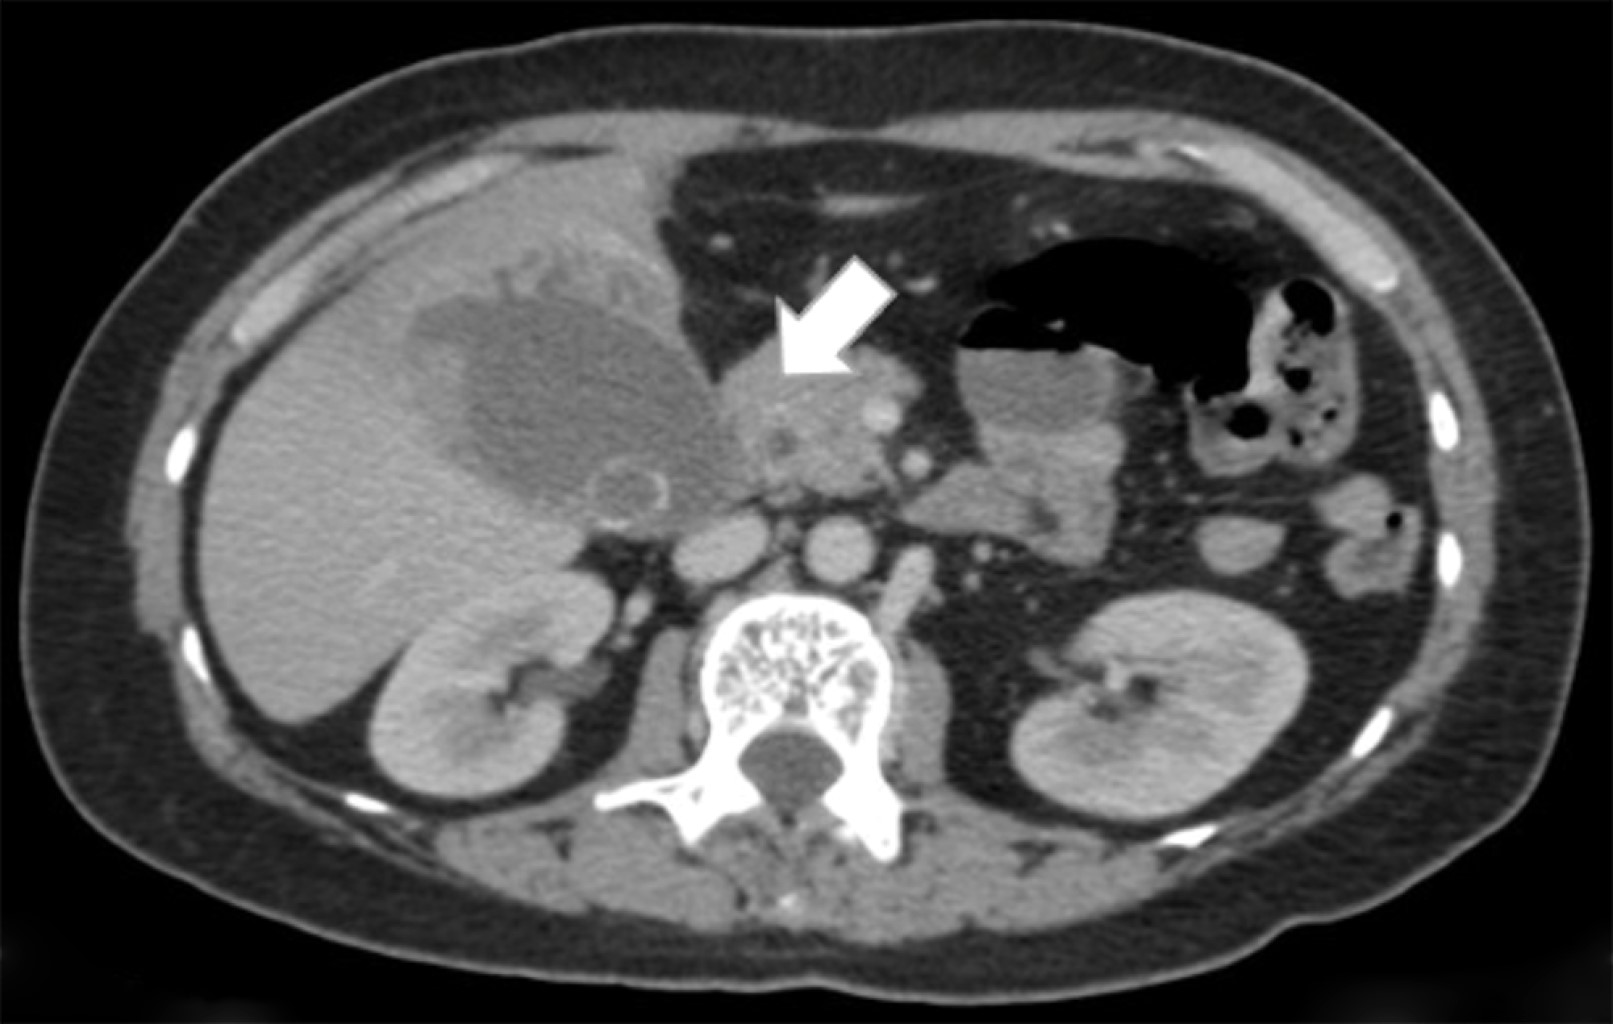

Se trata de paciente femenino de 55 años de edad quien acudió al servicio de urgencias con un cuadro de un mes de evolución caracterizado por dolor abdominal localizado en epigastrio e hipocondrio derecho, irradiado a región interescapular, mismo que fue aumentando, por lo que decidió acudir con facultativo quien inició manejo homeopático; sin embargo, no presentó mejoría, por lo que acudió al servicio de urgencias de nuestra unidad hospitalaria donde se registraron los siguientes signos vitales: TA (tensión arterial) 114/76 mmHg, Fc (frecuencia cardiaca) 124 lpm, Fr (frecuencia respiratoria) 16 rpm, temperatura 36 oC. Al interrogatorio la paciente negó la presencia de fiebre, náusea, vómito o presencia de evacuaciones disminuidas en consistencia. Para su abordaje se solicitaron laboratorios generales, de los cuales destacan la presencia de leucocitosis (12,300 mm3), elevación de fosfatasa alcalina y GGT (315 y 268 U/l respectivamente); se solicitó una tomografía computarizada de abdomen con contraste intravenoso (Figuras 1, 2 y 3) que evidenció la presencia de vesícula biliar con litos en su interior, impactados y ruptura intrahepática, además de un absceso intrahepático en segmentos IV y V (Figura 2).